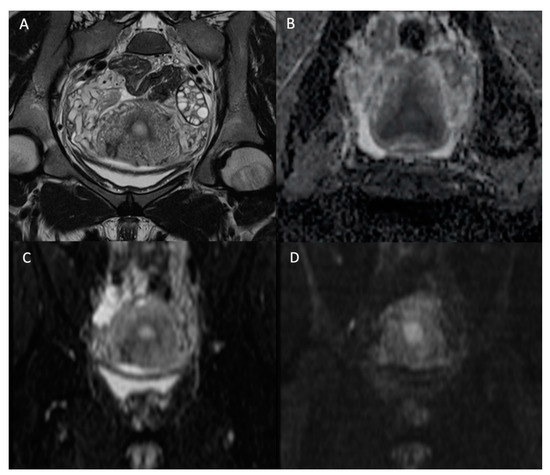

To this day, the monoexponential model keeps the high ground in routinely performed prostate mpMRI, due to its rapid processing and interpretation based on the ADC map. Such a monoparametric model is well integrated as a routine clinical standard [47]. Furthermore, its diagnostic performance was considered superior to the IVIM model [48,54]. In a recent study, the DKI model was not found superior to the monoexponential model for the detection of clinically significant cancers [55]. However, as suggested in the prostate imaging–reporting and data system (PI-RADS) guidelines, it is essential to interpret the ADC map in conjunction with the native DW images [45]. Figure 6 illustrates a neoplastic nodule arising in the peripheral zone of the prostate, appearing with lower ADC values in combination with a hyperintense focus on high b-values images. Such findings are typical for reduced diffusion inside a tumor area as a consequence of the high cellularity. Cellular density quantitatively measured by histological techniques was shown to be negatively correlated to ADC values [56,57]. Studies based on the comparison between axial DW images and histological slides have reported a negative correlation between ADC values and the differentiation grade of the tumor tissue—the Gleason score [58], which is more conspicuous in the peripheral zone than in the transition zone [59].

Figure 6.

MR images of a prostate MRI at 3T in a 78-year-old man with a 7.7 ng/mL PSA. (A) The axial T2W morphologic image shows a hypointense area (arrows) expanding in the peripheral zone of the prostatic parenchyma on both sides with a predominant tissular infiltration on the left side. (B) The corresponding ADC map obtained by fitting a monoexponential model using the b-50 (C) and b-1500 (D) images. As a typical example of high-grade prostate adenocarcinoma, the b-50 (C) to b-1500 (D) images show an increasing signal in the neoplastic tissue due to the diffusion restriction properties in histology proven Gleason 9 prostate carcinoma. These MR findings were reported as a PI-RADS 5.

The essential role of the diffusion technique in prostate imaging is well illustrated by the PI-RADS score. This scoring system was established by a conjoined representation of the American College of Radiology (ACR), the European Society of Urogenital Radiology (ESUR) and the AdMeTech Foundation. The PI-RADS score ranges from 1 to 5, with normal MR findings (1) to MR findings highly suspicious of malignant prostate neoplasia (5). The 1.0 version was published in 2012 then followed by the 2.0 version in 2014 and the 2.1 version in 2019 [60,61,62]. Across versions 1.0 to 2.0, major changes revealed the role of diffusion imaging in prostate cancer detection. In version 1.0, all sequences performed in prostate MRI (T2W, DWI and DCE) were considered equal for cancer detection. Since PI-RADS version 2.0, DWI constitutes a key factor of appreciation. In the peripheral zone of the prostate, the PI-RADS score of tumor suspicion is primarily based on the diffusion findings as illustrated in Figure 6. In the transition zone, the parenchyma may be modified by stromal and glandular hyperplasia resulting in a complex and chaotic tissue that requires the anatomical information provided by T2W sequences. However, DWI is essential to complete the analysis, allowing to upgrade “equivocal areas” to higher PI-RADS score lesions. In a recent study, the performance of the PI-RADS score in prostate cancer detection was characterized by a high negative predictive value (NPV) of 94.1% for a PI-RADS cutoff at 3 and an NPV of 85.5% with a cutoff at 4 [63]. Prostate MRI examination provides a valuable tool for cancer risk stratification. However, a meta-analysis found the NPV of mpMRI to range from 63% to 98% illustrating the remaining limitations to detecting significant prostate cancer lesions in some patients [64,65]. The new version 2.1 of the PI-RADS score holds DWI as a reference for the detection of significant prostate cancer in the peripheral zone and as a highly valuable support tool for the transition zone next to the dominant T2W sequence.